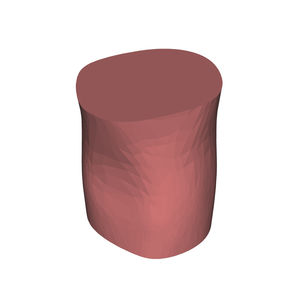

Anatomisches Modell / Schulter HUM-Efür Punktionenfür Injektionenfür Ultraschalluntersuchungen

- Körperteil

- Schulter

- Farbe

- rosa

Echogene und röntgendichte anatomische Schaufensterpuppen

für eine bessere Ausbildung in interventionellen Verfahren unter Ultraschall und Röntgenstrahlen

Identifizierung anatomischer Orientierungspunkte mit Ultraschall und Röntgenstrahlen

Training für Punktion und Infiltration unter Ultraschall und Röntgenstrahlen

Hautgetreues Stichempfinden mittels Echo und Radio

Alle unsere Schaufensterpuppen sind echogen und röntgendicht und können bis zu 600 Injektionen pro Stelle tragen.